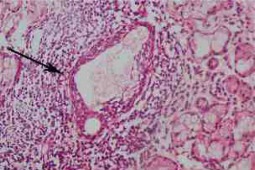

Przeanalizowano dane 7748 kobiet i 562 mężczyzn z rozpoznaniem PZS leczonych w 20 ośrodkach klinicznych usytuowanych na pięciu kontynentach. Zdecydowaną większość, bo aż 78% (6174) stanowili chorzy rasy białej, 1066 (14%) miało pochodzenie azjatyckie, 393 (5%) – latynoamerykańskie, 103 (1%) afro-amerykańskie, a 147 (2%) miało inne pochodzenie. U afro amerykanów chorobę rozpoznano średnio o 7 lat wcześniej w porównaniu z chorymi rasy białej. Porównując stosunek chorych kobiet i mężczyzn największe dysproporcje zaobserwowano u Azjatów 27:1, a najmniejsze wśród Aforamerykanów: 7:1. Częstość zgłaszania objawów suchości (jamy ustnej i oka) była najniższa u chorych pochodzenia azjatyckiego, a najwyższy odsetek dodatniego wyniku biopsji ślinianki odnotowano u chorych rasy białej i latynoamerykańskiej.